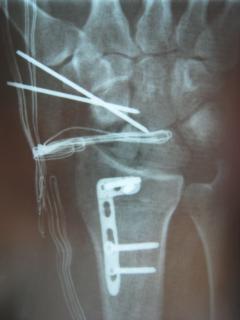

Η αντιμετώπιση της ψευδάρθρωσης του σκαφοειδούς είναι πάντοτε χειρουργική. Με ραχιαία ή παλαμιαία προσπέλαση αποκαθίσταται ο άξονας του σκαφοειδούς και σταθεροποιείται το σκαφοειδές με ειδική βίδα ή βελόνες, με παράλληλη τοποθέτηση οστικών μοσχευμάτων. Μπορεί επιπλέον να γίνει και οστεοτομία κλειστής σφήνας του περιφερικού άκρου της κερκίδος. Στις περιπτώσεις άσηπτης νέκρωσης το μόσχευμα πρέπει να είναι αγγειούμενο – για να προσδώσει αιμάτωση στο νεκρωμένο κεντρικό τμήμα – και λαμβάνεται με μικροχειρουργικές τεχνικές από το περιφερικό τμήμα της κερκίδος ή από άλλα τμήματα του σώματος

Περίπτωση 2: Μετεγχειρητικά 1

Περίπτωση 2: Μετεγχειρητικά 2